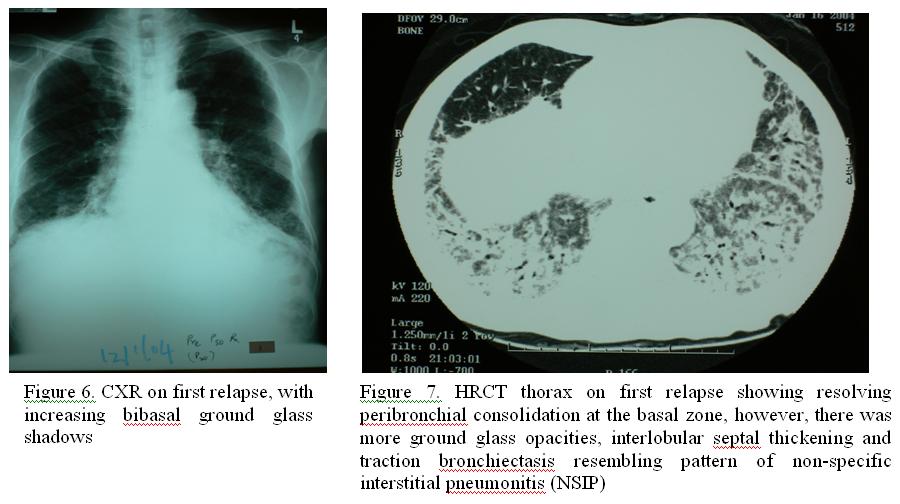

Steroid was tapered down to 20mg daily within 8 weeks’ time . Thereafter, the patient developed low grade fever and shortness of breath. Increased bibasal ground glass shadows was noted in chest radiograph (Figure 6). At the same time, there was mild proximal muscle weakness with creatine phosphokinase (CPK) elevated to ~1200U/L, facial rash was also noted. Vasculitic markers like ANCA, Anti-ENA, anti-Jo 1 antibodies were negative, HRCT thorax showed resolving peribronchial consolidation at the basal zone, and there was more ground glass opacities , interlobular septal thickening and traction bronchiectasis resembling pattern of non-specific interstitial pneumonitis (NSIP) ( Figure 7).

This condition was compatible with relapse of BOOP with elements of NSIP and underlying dermatomyositis. Hence, prednisolone was stepped up to 50mg daily once again, coupled with intavenous tazocin to cover for possible infective elements.